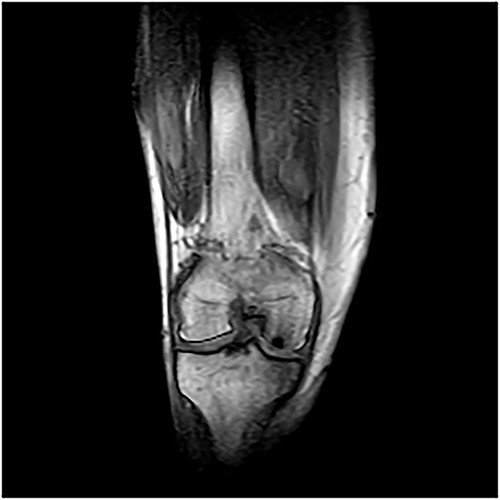

A 55-year-old male patient with a history of knee pain and difficulty with weight-bearing activities on the right side underwent arthroscopic repair of a large cartilage defect in his knee with MCA derived from his own knee cartilage (Figs 1, 2).